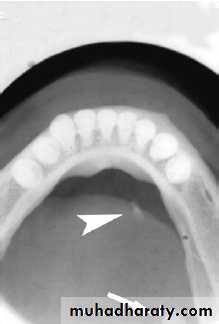

Ectopic/aberrant salivary gland tissue\Stafne bone cyst- most common ectopic salivary tissue .

Asymptomatic

clearly demarcated radiolucency of the angle of the mandible.

below the inferior dental neurovascular bundle.

No treatment is required.